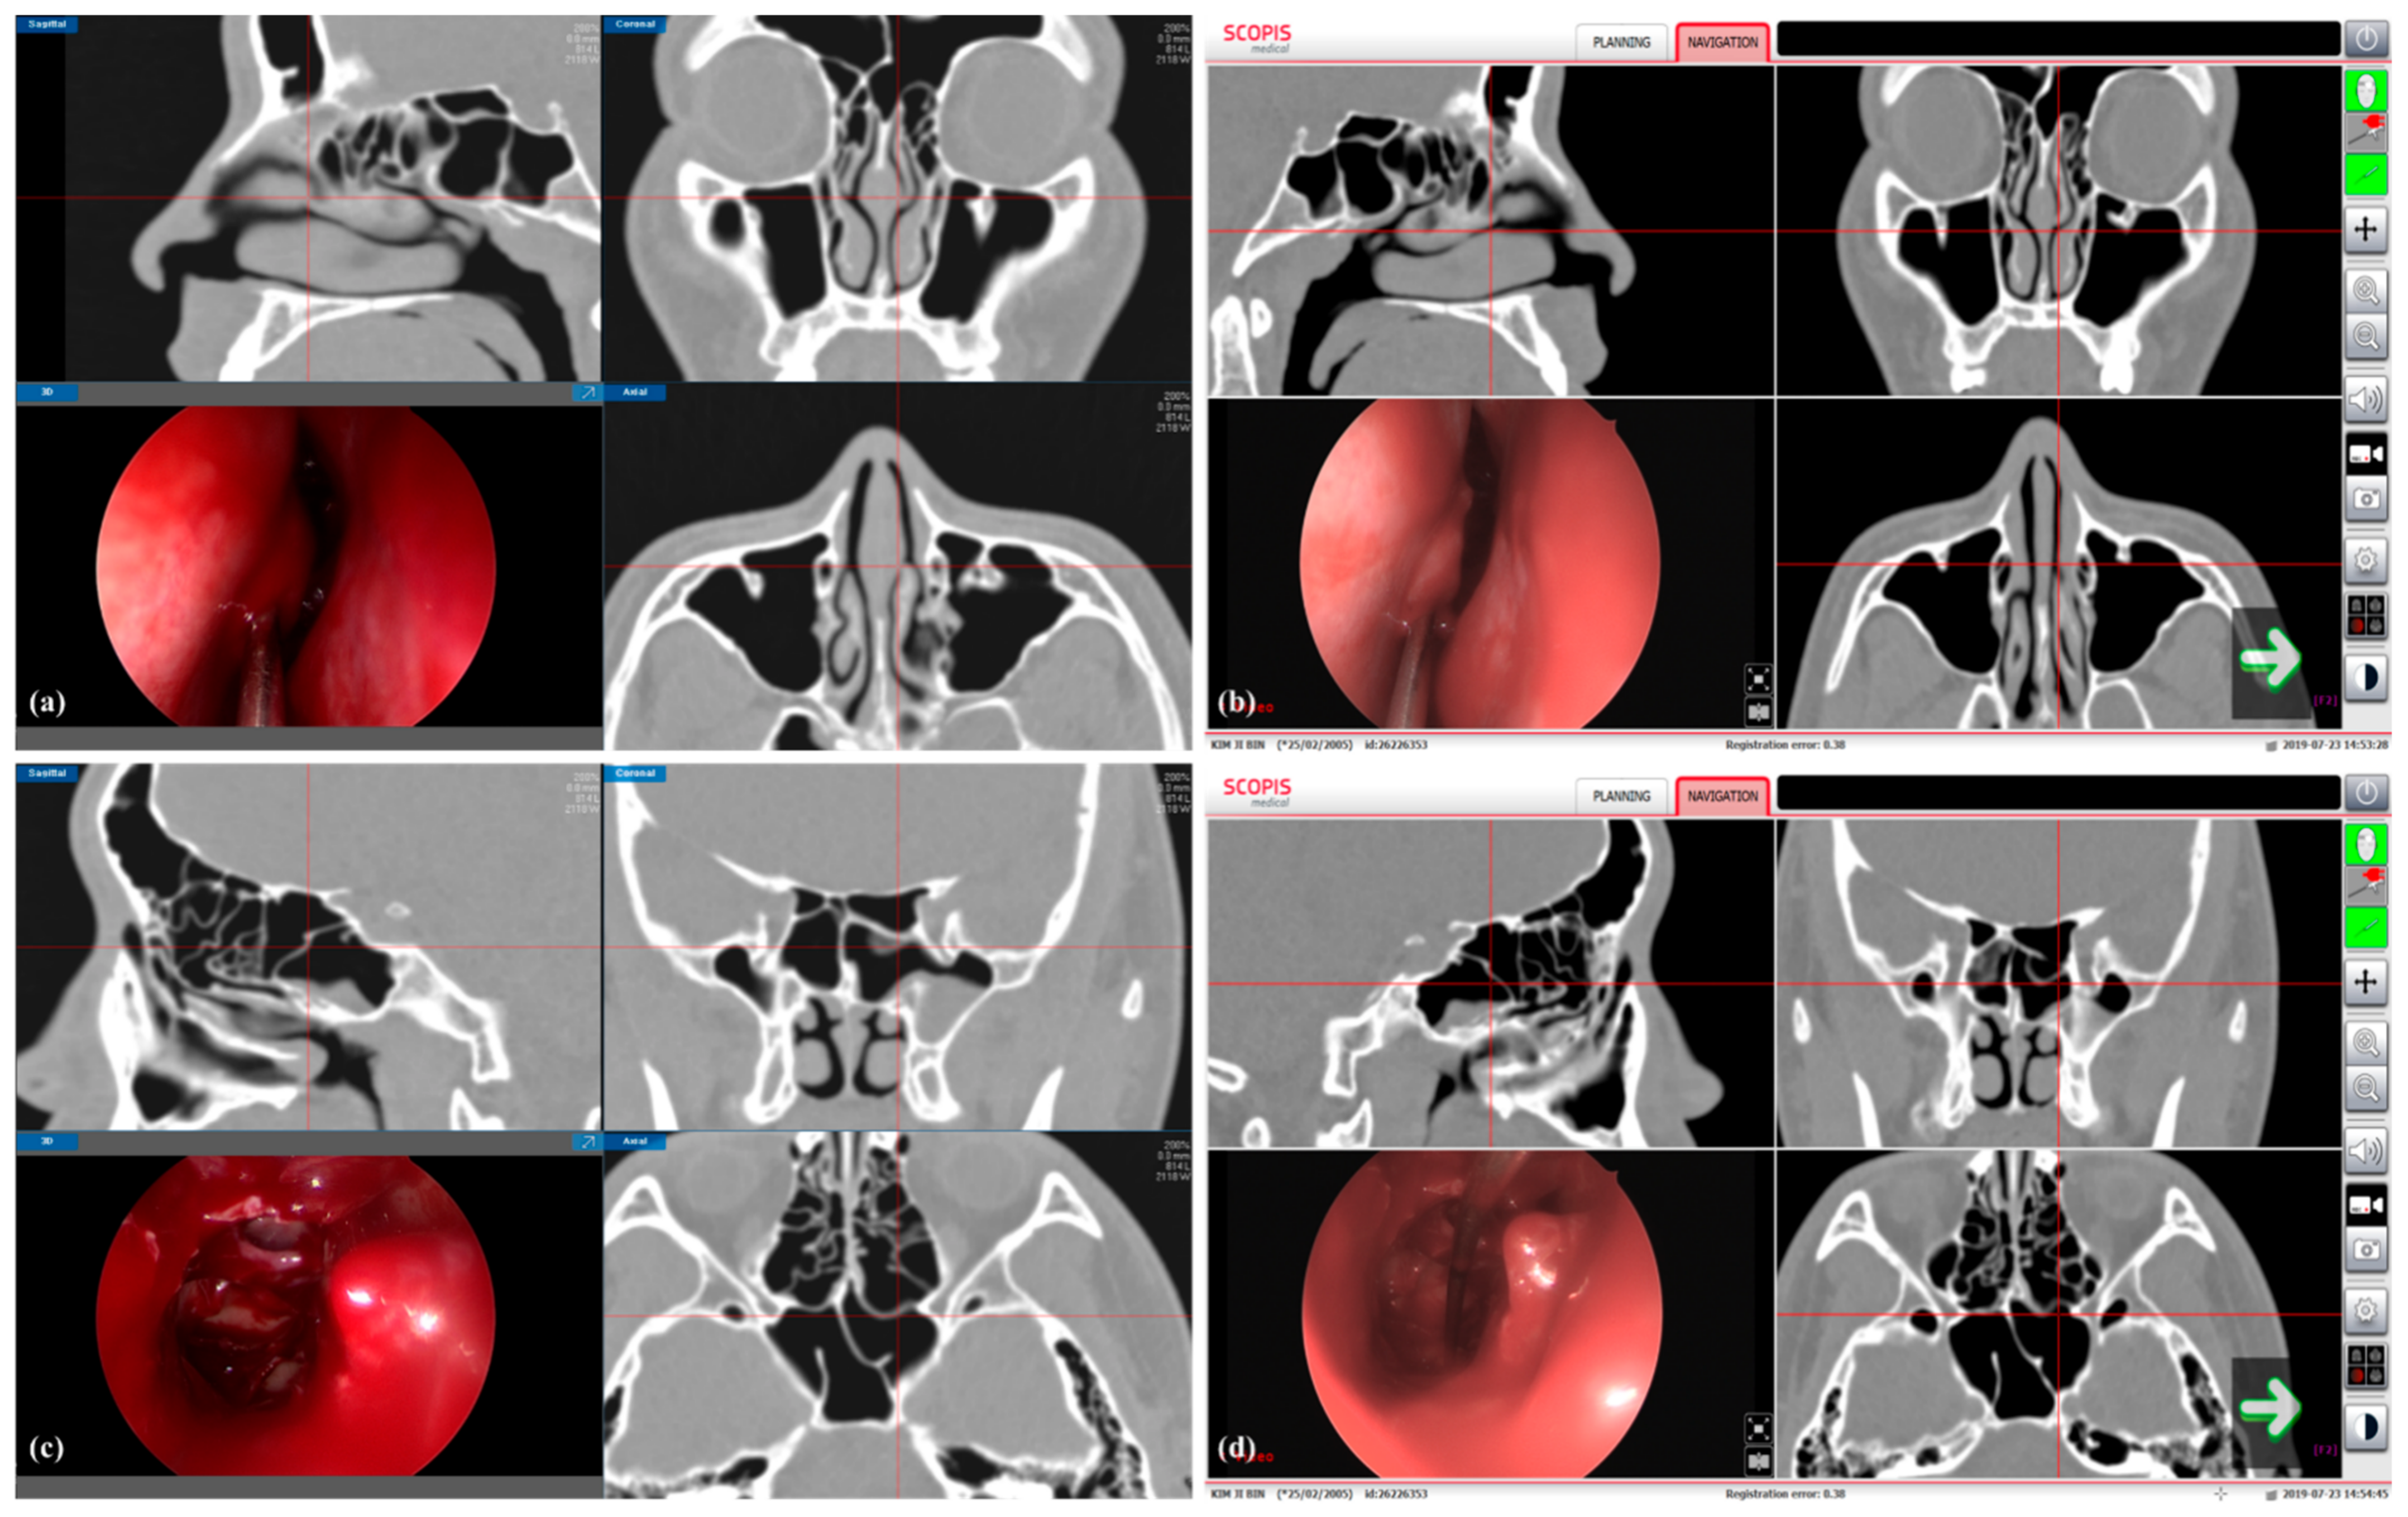

2.3. Image-Guided Endoscopic Sinus Surgery System with 3D Volumetric Visualization

2.5. Image-Guided Endoscopic Sinus Surgery System with 3D Volumetric Visualization